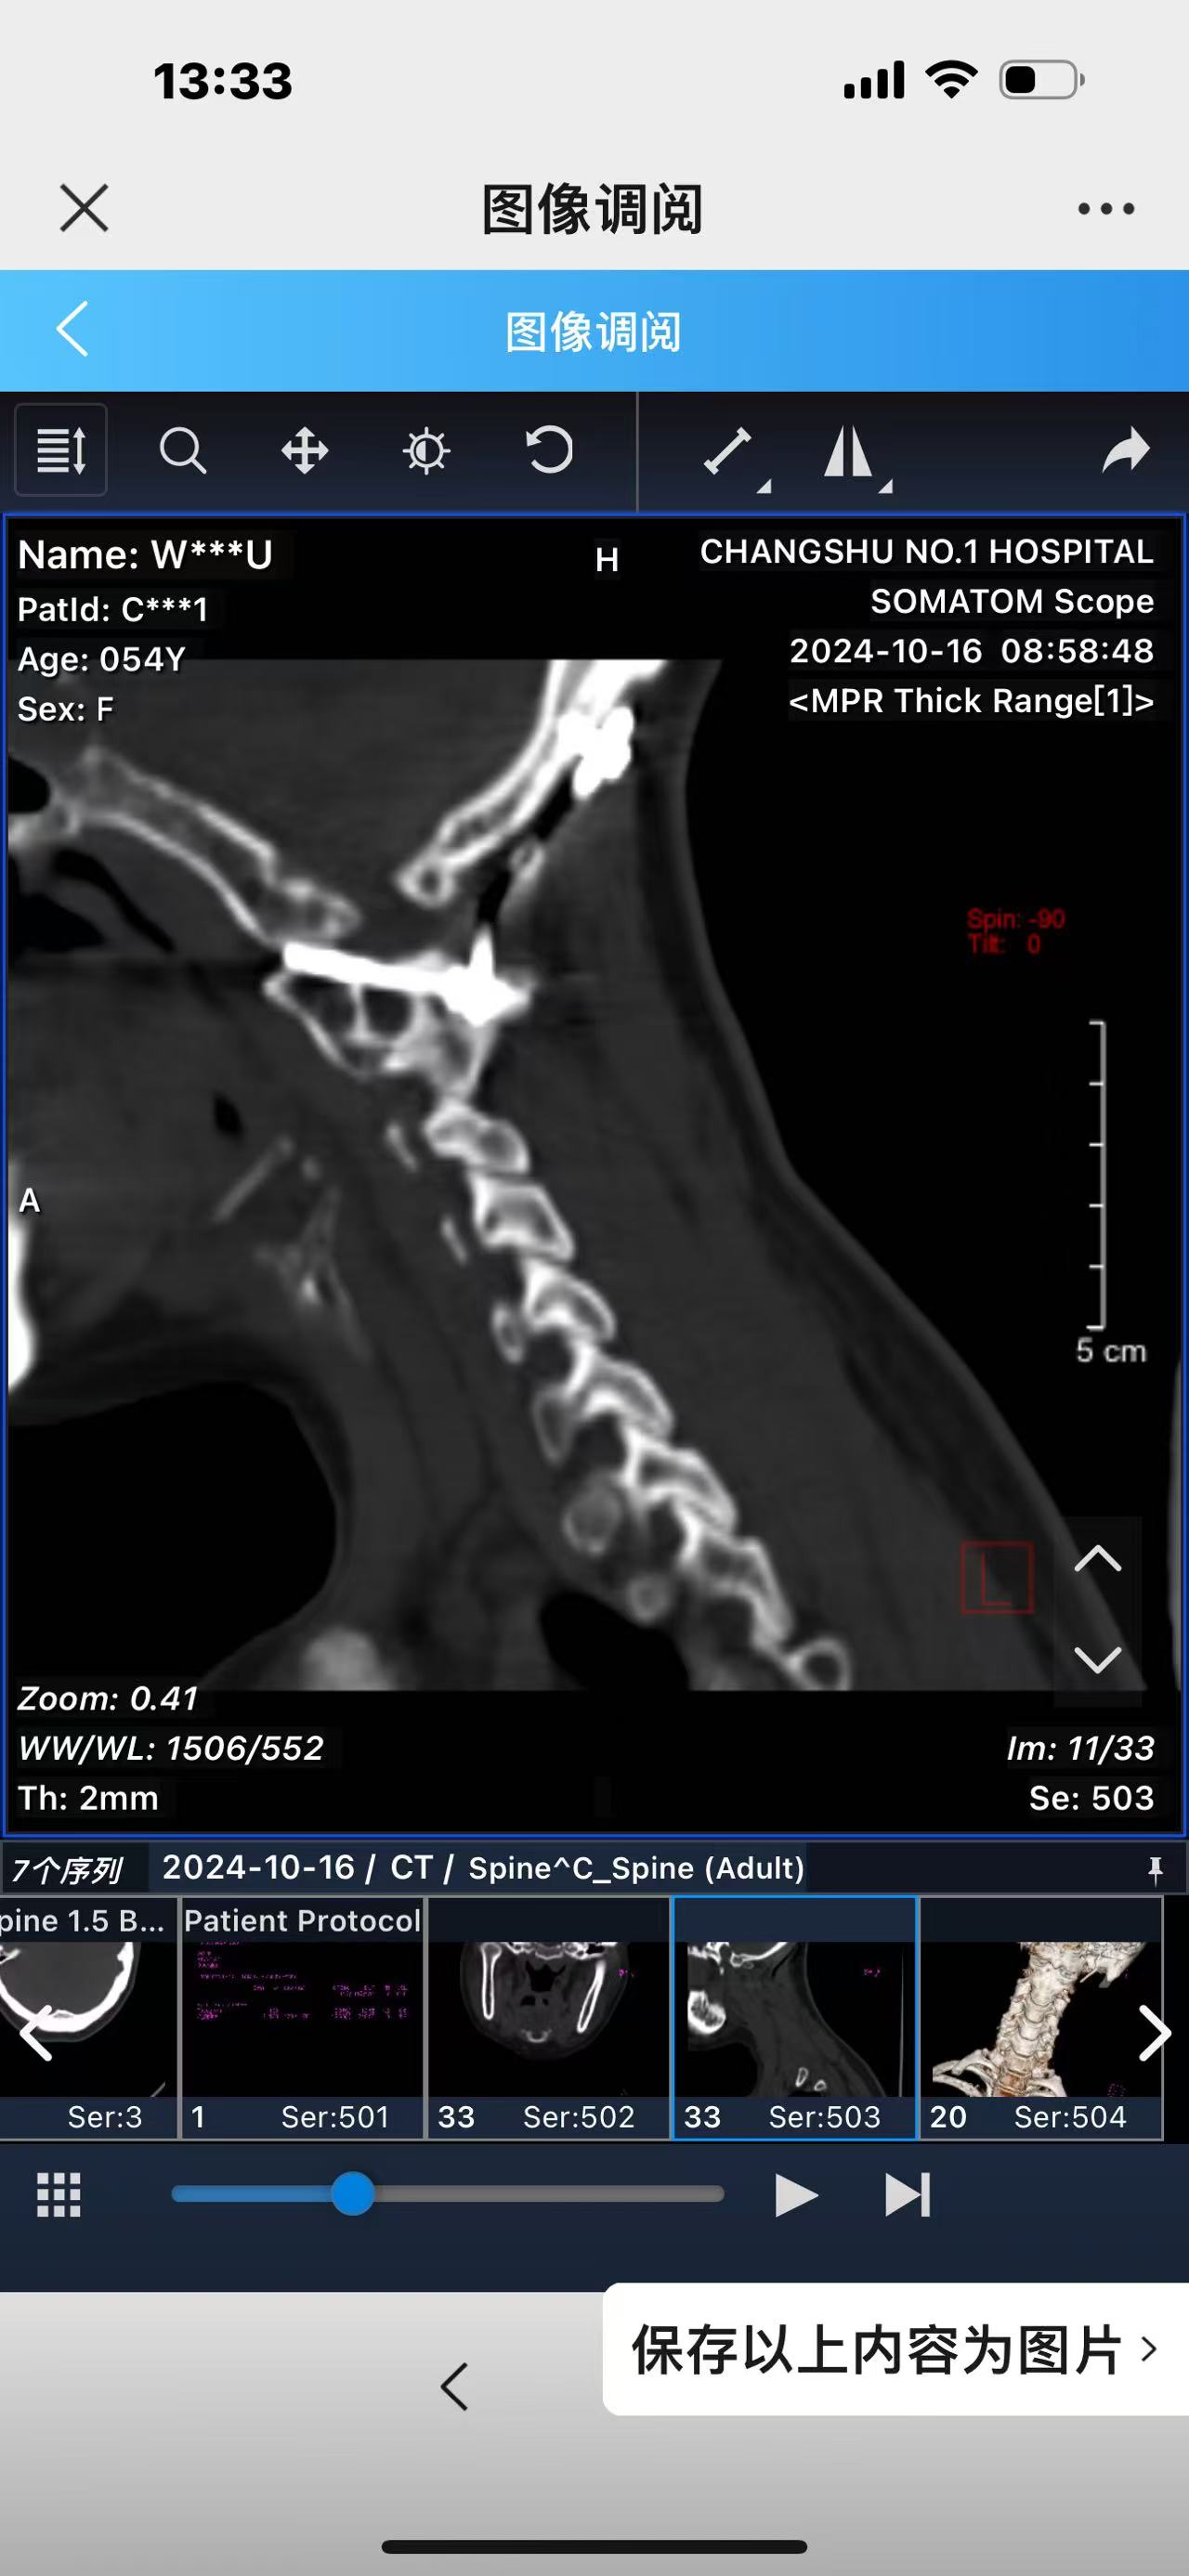

• 诊断:寰枢椎脱位,颅底凹陷

• 2024.10.20,复查,对位良好,偶尔会肩甲骨酸,坐下就不酸。